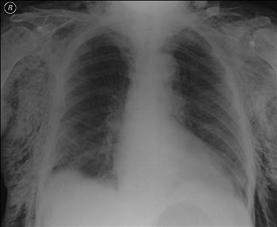

Contuzie pulmonara stanga Contuzie pulmonara dreapta

Contuzie pulmonara dreapta.Imagine CT